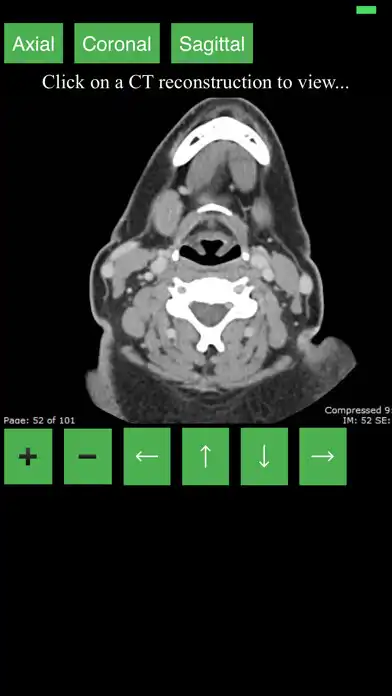

This app provides a dynamic and interactive method of viewing cross-sectional human anatomy on computed tomography (CT). The information contained in this app cannot be guaranteed for completeness and accuracy.

- Labeling of anatomical parts

- 3D Anatomic localization